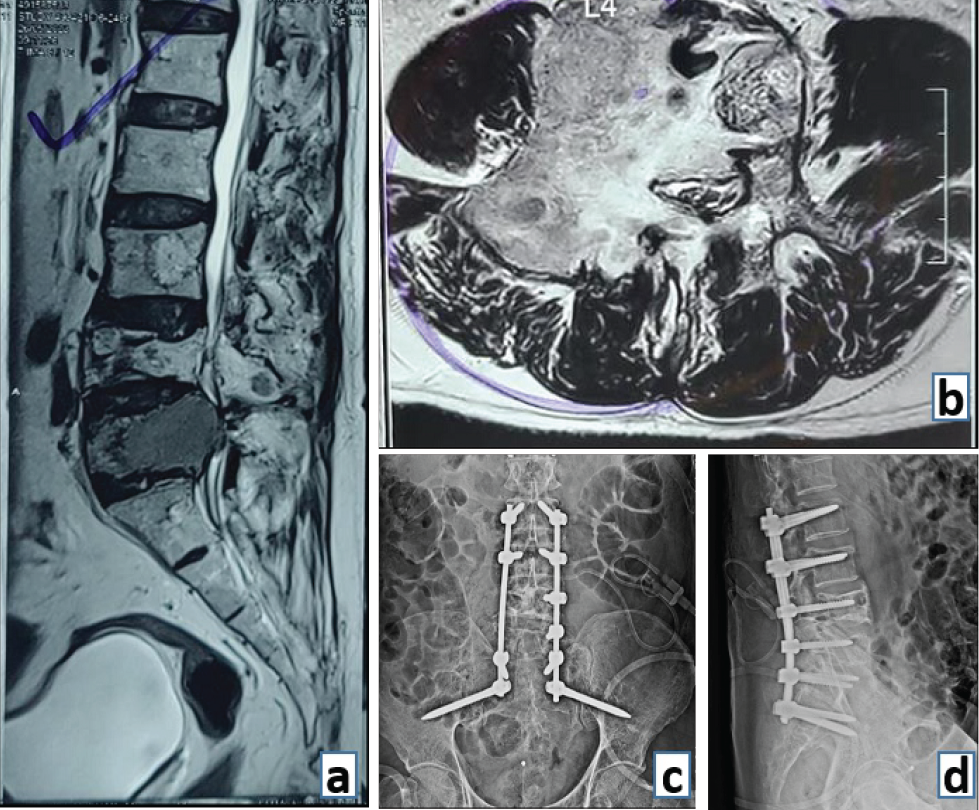

For instance, patients stabilized with terminal spinal metastatic disease may have a limited life span to achieve bony fusion. Moreover, their bone healing capacity is often compromised due to continuous chemoradiotherapy and poor nutritional status. For these reasons, the goals of spinal stabilization (with or without cement augmentation) in oncology patients include preservation of neurology, pain relief, arrest of progression of spinal deformity with an improved quality of life and overall survival (Fig. 4). Fusion may not be an essential prerequisite to achieve these goals. However, spinal stabilization with internal bracing is effective [6].

Figure 4: (a) Preoperative sagittal magnetic resonance imaging (MRI) film demonstrating an expansile lytic lesion of multiple myeloma at L4 vertebral level (sacralised L5). (b) Preoperative axial MRI image showing the extent of vertebral body involvement and the posterior elements at L4 level. (c) Post-operative anterior and (d) lateral radiograph demonstrating lumbopelvic stabilization of the spinal column in a case of multiple myeloma.